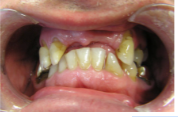

1) 1. Initial situation of teeth anterior and lateral view

3. Presence of teeth

-UR7--- UR3UR2---UL3UL4UL5----

-LR7LR6--LR3LR2LR1LL1LL2LL3LL4--LR6--

4) Restorations of upper and lower teeth